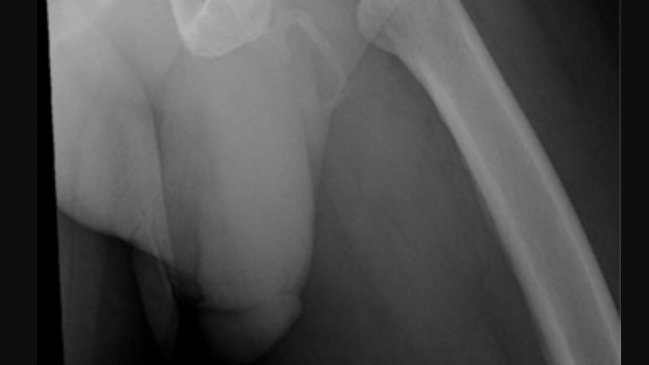

Los resultados mostraron que el miembro se le estaba convirtiendo en hueso y se veía nítida en los rayos x. Tan extraña es esta patología que fue publicada en la revista Urology Case Reports.

"La osificación del pene, una condición rara, se ha relacionado con la enfermedad de Peyronie. La osificación se lleva a cabo generalmente en la mitad del eje del pene con pocos casos en todo el eje, como en éste", dice el estudio.

Hay menos de 40 casos en el mundo de esta enfermedad, que consiste en la calcificación de los tejidos blandos. La placa endurecida reduce la flexibilidad y provoca una curvatura durante la erección, lo que redunda en disfunción eréctil.